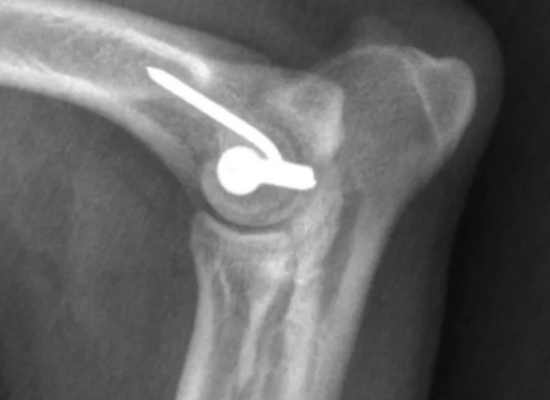

1. Pose de vis transcondylienne

Méthode la plus courante :

une vis est fixée entre les deux condyles pour stabiliser la fissure.

La prise en charge chirurgicale demeure aujourd’hui l’option thérapeutique la plus efficace, avec un excellent pronostic de récupération fonctionnelle. L’intervention consiste le plus souvent en la mise en place d’une vis transcondylienne, pouvant être appliquée en compression afin d’optimiser la stabilité osseuse.Cette vis peut-être mise en place de manière minmallement invasive.

Cette approche chirurgicale réduit significativement le risque de complications ultérieures, notamment en cas d’ossification incomplète ou de fragilité structurelle du condyle huméral. Selon les préférences et l’expertise du chirurgien, il est parfois recommandé d’ajouter une plaque ou une broche au niveau de la crête épicondylaire, renforçant ainsi la fixation et sécurisant davantage la consolidation.